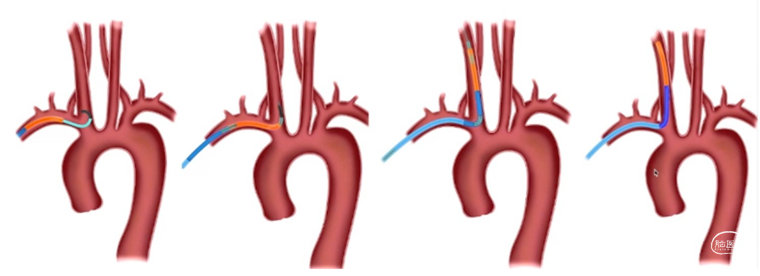

2、可选择对侧桡动脉置入6F动脉鞘,单弯或西蒙导管将0.035泥鳅导丝置于病灶侧锁骨下动脉起到牵拉作用。

3、将6F导引导管到达狭窄椎动脉附近,微导丝导引球囊扩张支架(4-5mm)铆定狭窄部位后扩张释放支架。

备注:6F导引导管可兼容0.035 in泥鳅导丝和球囊扩张支架(4-5mm),5mm支架通过略涩。

(二)高位椎动脉狭窄经绕同侧入路椎动脉狭窄支架置入

1、椎动脉狭窄,如果开口向外侧,行同侧桡动脉入路时角度顺行,可选择同侧桡动脉置入6F动脉鞘,0.035泥鳅导丝置于病灶侧锁骨下动脉起到或单弯同轴将6F导引导管到达狭窄椎动脉附近,微导丝导引球囊扩张支架(4-5mm)铆定狭窄部位后扩张释放支架。

1、双侧桡动脉置入6F动脉鞘。健侧进行造影定位和观察。

患侧将0.035in泥鳅导丝通过狭窄进行小球囊扩张(3-3.5mm)建立通路,撤出球囊。

沿泥鳅导丝(不用导引导管)将7-10mm球扩支架到位,通过对侧造影铆定后球囊扩张释放。

2、输送7-10mm球扩支架时不需要导引导管,直接沿泥鳅导丝输送,球扩支架不释放时小于2.5mm,能够顺利通过桡动脉。